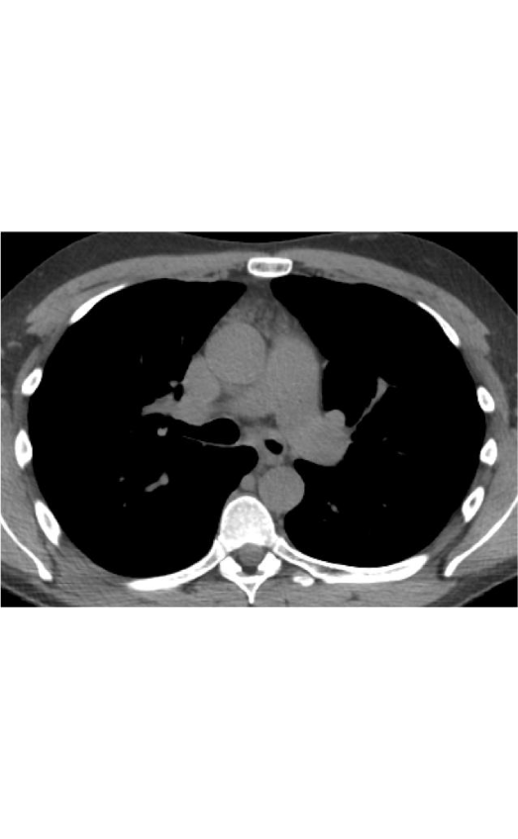

In this case you can see subtle apical centrilobuar emphysema